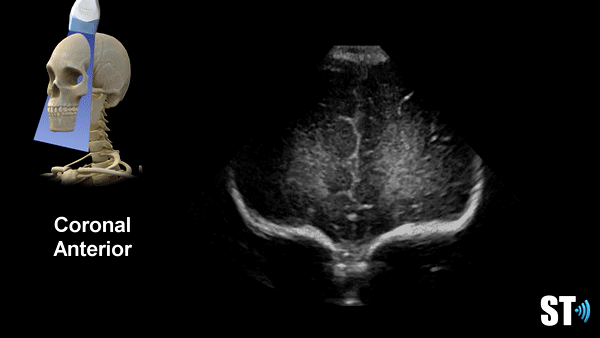

We use primarily the anterior fontanelle using a coronal, sagittal and parasagittal views. Also we scan through the mastoid fontanelle (for the posterior fossa and cerebellar views) and posterior fontanelle (for posterior structures especially the occipital horn to detect dependent hemorrhage) and temporal views for further evaluation.

Coronal Anterior Fontanelle Views